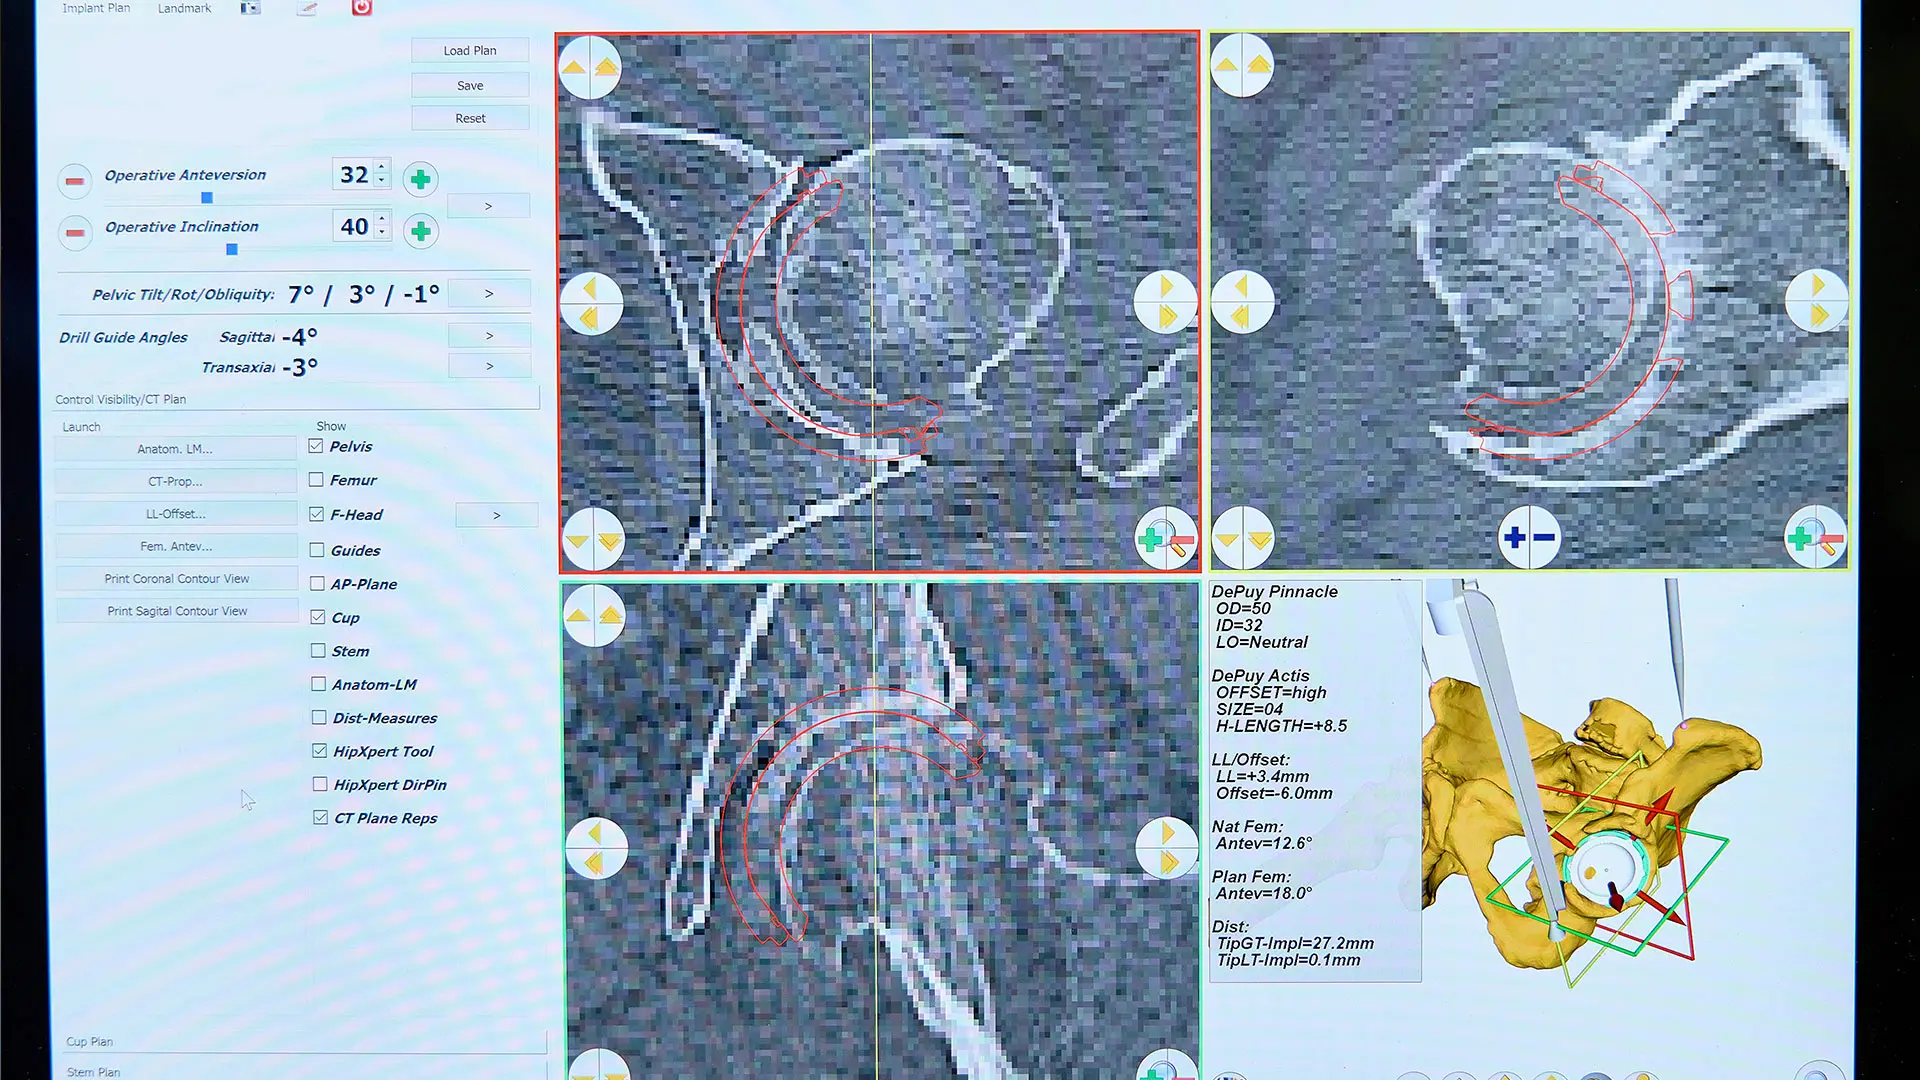

CT based, three-dimensional patient specific plan for total hip replacement

Cleared by the United States Food and Drug Administration in February 2021, AR technology is designed as an alternative to robotic systems, characterized by bulky workstations, cameras, and screens, with low-profile systems that no longer require the surgeon to constantly look back and forth between patient and monitor. Instead, 3D holograms now fill the surgeon’s field of vision with more data and information than was previously possible. Specifically, augmented reality digitally overlays the preoperative CT scan and detailed surgical reconstruction plan on top of the patient’s anatomy as seen real-time by the surgeon via tracking and registration technologies. This capability allows for accurate alignment and placement of the implant.

“The AR software allows the surgeon to effectively compare the CT scan to what they’re actually seeing inside the patient,” explains Dr. Hayden, who is Assistant Professor of Orthopedic Surgery at the Icahn School of Medicine at Mount Sinai. “That lets you know the fidelity of the registration and if the 3D plan is correctly aligned.”